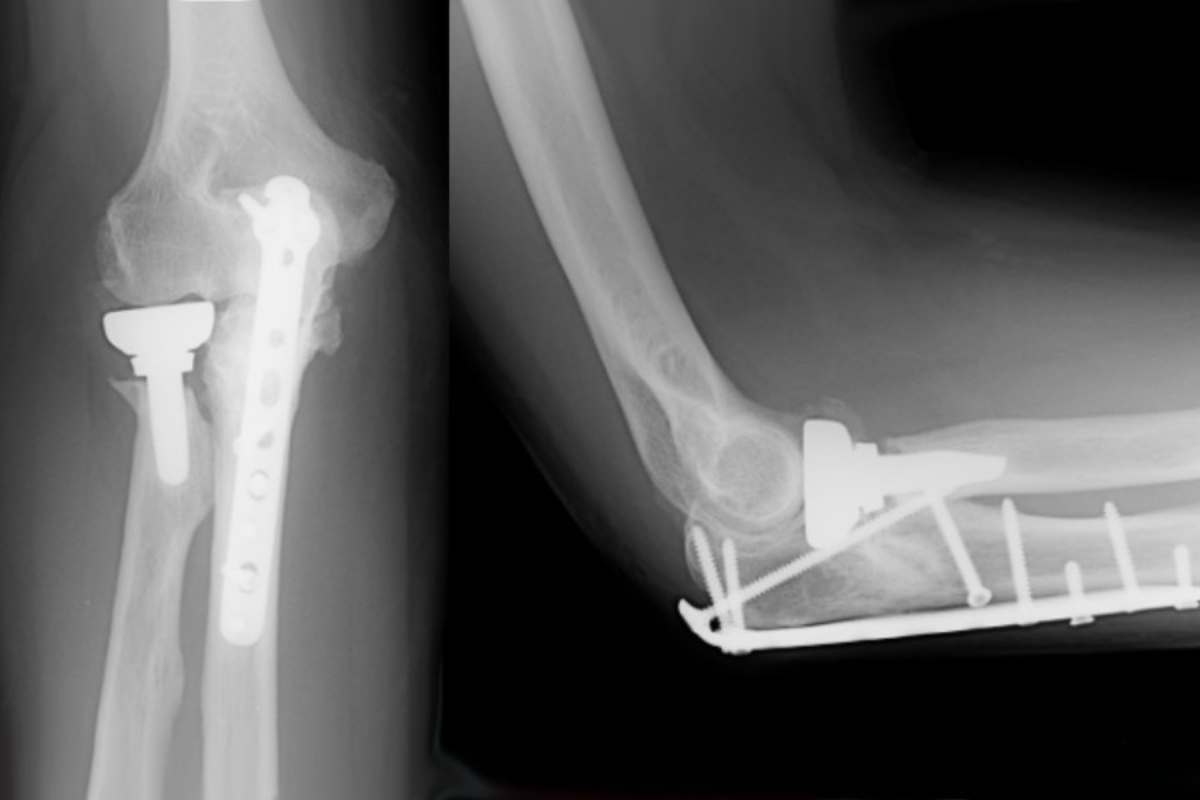

Expert surgical care for complex fractures, ensuring precise reconstruction and faster recovery.